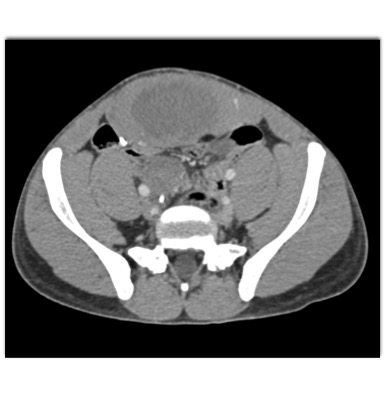

In this patient with a history Familial Polyposis (FAP) the best diagnosis is?

CTisus Quiz   CTisus Quiz

lymphoma

post op seroma

desmoid tumor

abdominal wall seroma